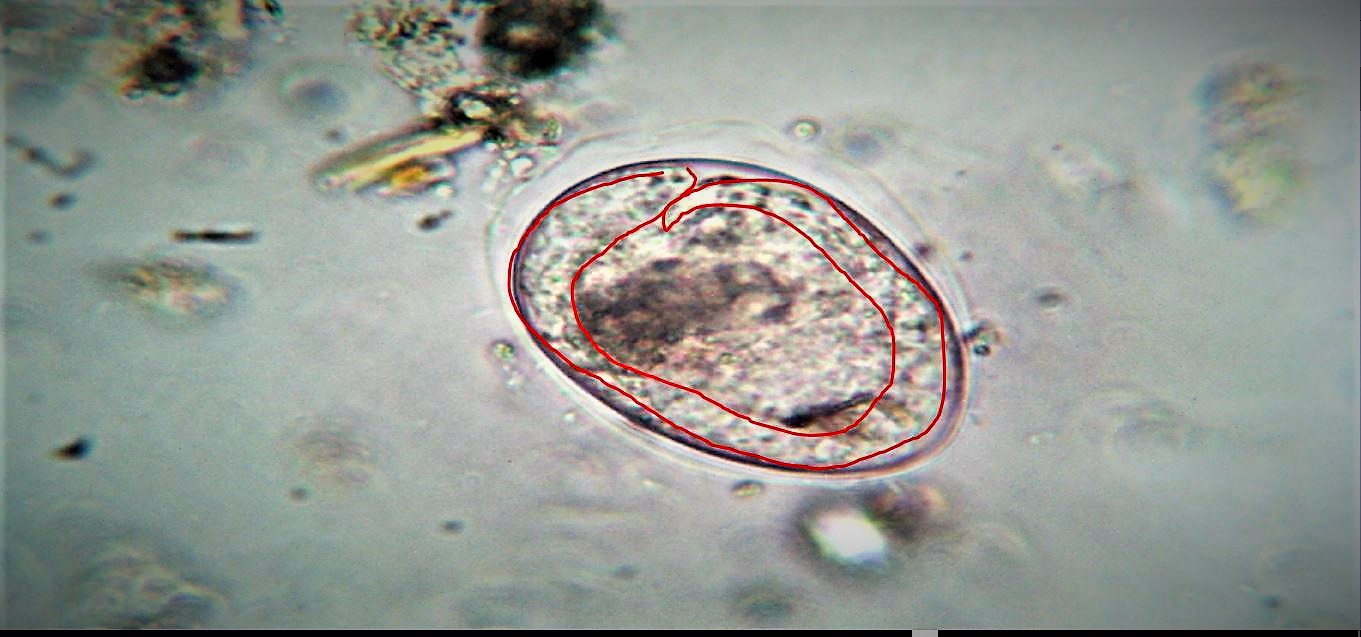

come asserito da un parassitologo dovrebbero essere Ancylostoma e Ancylostomidiae sp.

Immagine:

nematode

180,47 KB